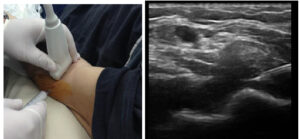

Punctie ecoghidata la nivelul tecii tendonului lung al bicepsului brahial si infiltratie AIS